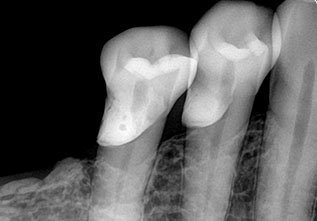

This dental procedure code, refers to a type of X-ray known as periapical. This term is used because these X-rays capture the entire tooth all the way down to the tissues at the tip of the tooth root – an area referred to as the periapical area.

A periapical X-ray will show one or two teeth in their entirety in one single image, right from the crown of the tooth which is the part exposed in the mouth to the very tips of the tooth roots located in the jawbone, as well as the surrounding bone supporting this tooth.